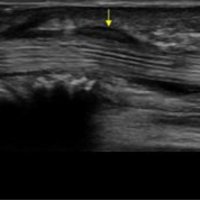

Thickening and hyper-vascularization of the A1 pulley are the hallmarks of trigger fingers on sonography. Other frequently observed features include distal flexor tendinosis and tenosynovitis.

The level of thickening can be variable with some authors suggesting the normal value being around 0.5 mm with thickening suggested when the diameter is over 1.1 mm.